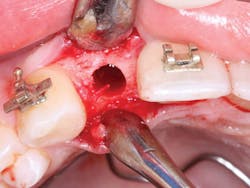

1. From a facial orientation, place the implant osteotomies in the center of the edentulous space from a mesial and distal orientation, using periapical radiographs to verify the parallelism and appropriate distance from the adjacent teeth (figure 3).

2. In the facial-lingual orientation, locate the osteotomies in the center of the ridge and parallel with the adjacent teeth. Use finger contact on the facial and lingual of the ridge while making the drill cuts. If you feel extra vibration on one or the other side of the ridge, reorient the drill appropriately (figures 4-7).

Figure 3: It is easy to center the implant osteotomy between the two adjacent teeth using your own clinical judgment and periapical radiographs.

Figures 4-7: This series of images shows a clinical situation, the cone beam images, and the freehand implant placement.